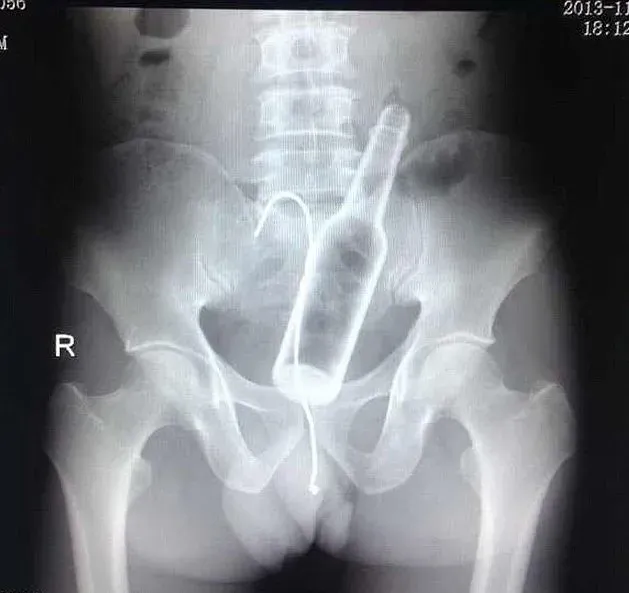

(2)진동기와 샐러드 집게:이 남성은 항문에 진동기가 끼어버리는 사고가 발생한다. 그래서 샐러드 집게로 빼내려하지만 불행히 그 집게도 끼어버렸다.